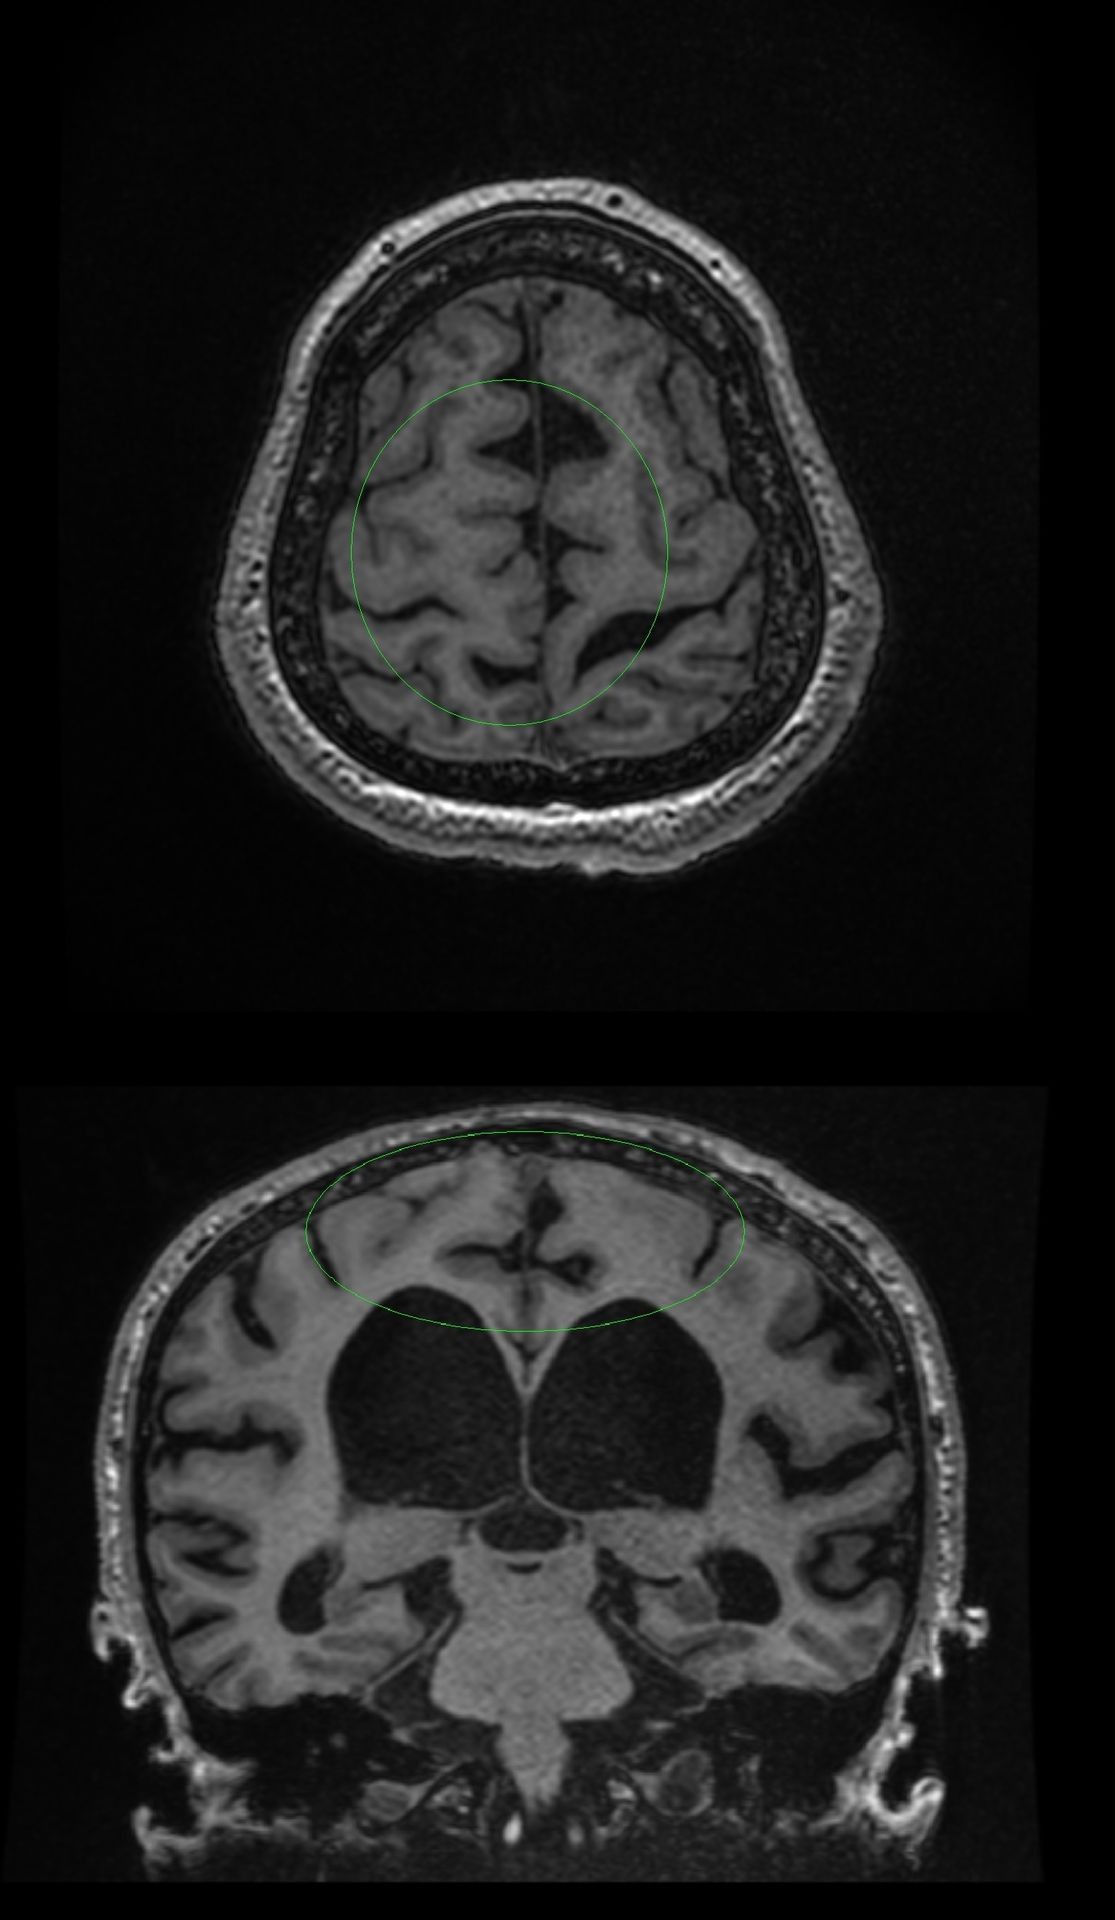

Primary endpoint of our prospective consecutive cohort study was to evaluate disproportionately enlarged subarachnoid spaces hydrocephalus (DESH) score, callosal angle (CA), cingulate sulcus sign (CSS) and Evan’s index of suspected idiopathic normal pressure hydrocephalus (iNPH) patients against the reference standard of lumbar infusion test (LIT) and external lumbar drainage (ELD) in prediction of gait response after ventriculoperitoneal (VP) shunt implantation in patients with iNPH. Patients were assigned to NPH and non-NPH groups based on LIT and ELD results. Age-matched controls were added for group comparison. 32 NPH, 46 non-NPH and 15 control subjects were enrolled in the study. There were significant differences in mean preoperative DESH scores of NPH, non-NPH and control groups (6.3 ± 2.3 ([±SD]) (range 2–10) vs 4.5 ± 2.4 (range 0–10) vs 1.0 ± 1.2 (range 0–4)). Differences in mean CA and Evan’s index were not significant between NPH and non-NPH groups. CSS showed 62.5% sensitivity, 60.87% specificity, 52.63% PPV and 70% NPV for differentiation of NPH and non-NPH groups. A CA of 68 degrees had 48.49% sensitivity, 76.09% specificity, 59.26% PPV 67.31% NPV and DESH score of 4 had 93.75% sensitivity, 41.30% specificity, 52.63% PPV and 90.48% NPV for differentiation between NPH and non-NPH groups.